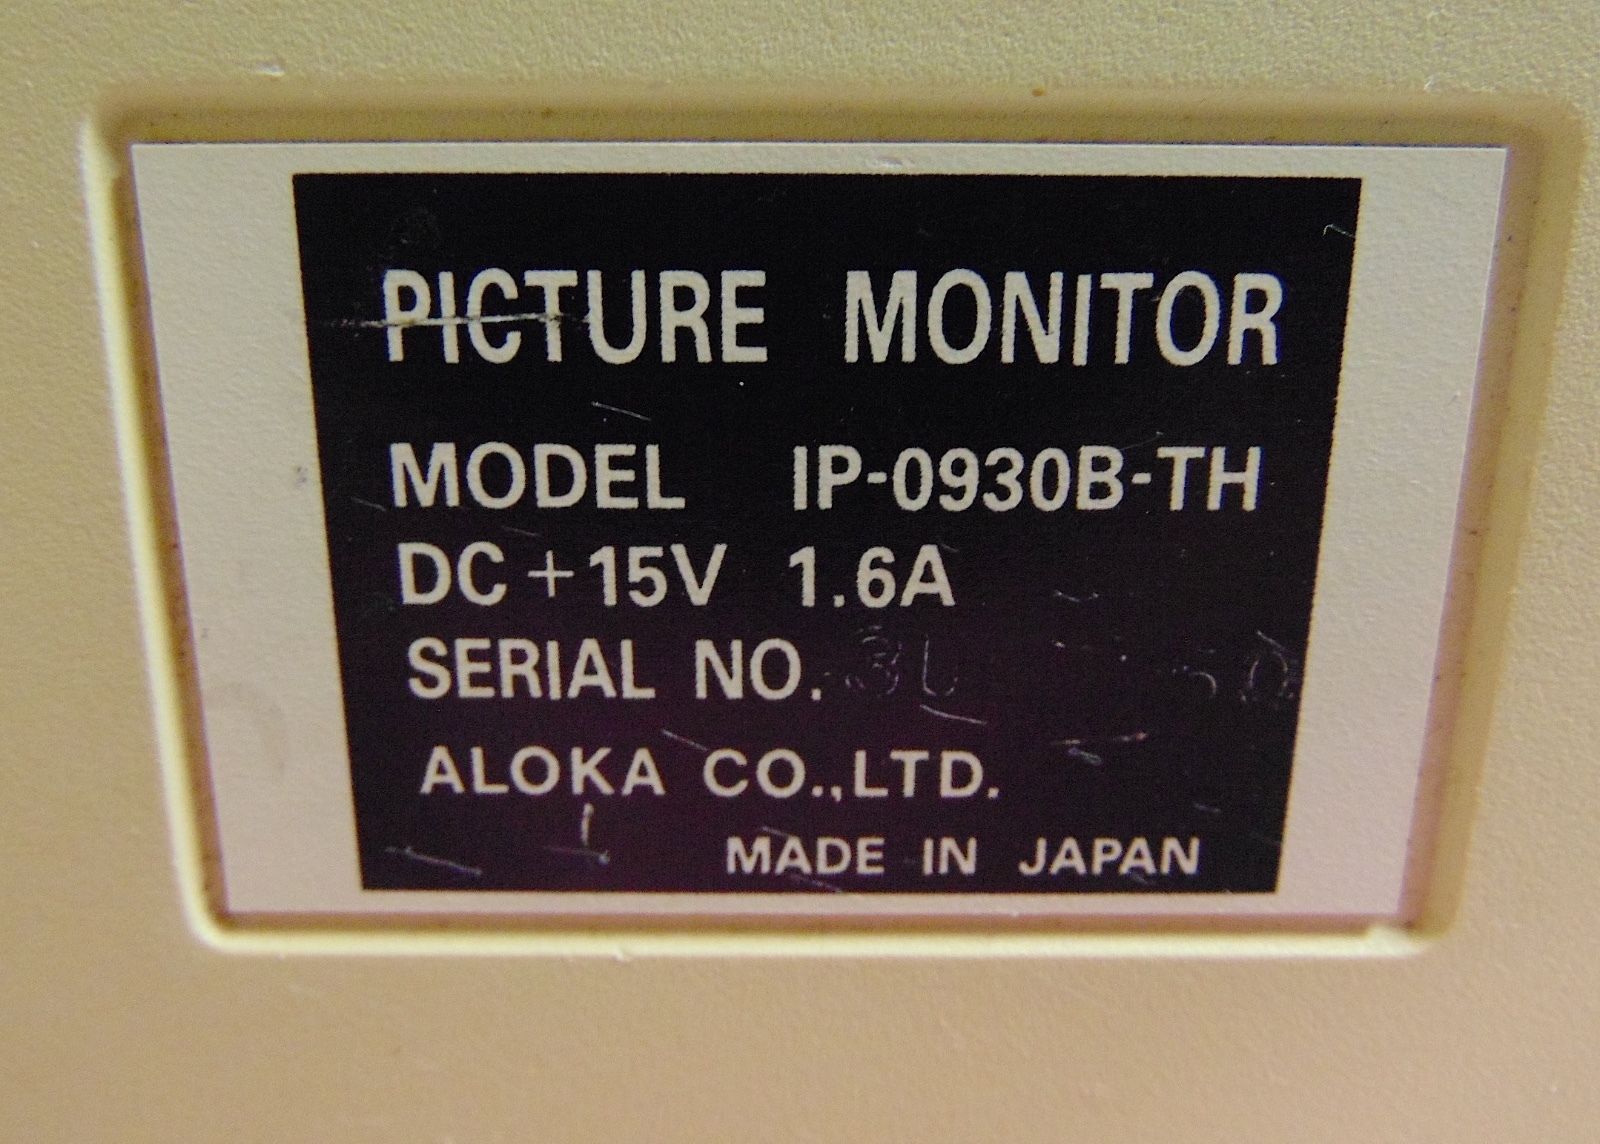

Seller Notes:âThe unit powers on and the monitor works good. Comes with a remote control unit and a functioning ultrasound probe. Unit is in good cosmetic condition but does show wear from being used.â

Country/Region of Manufacture: Japan